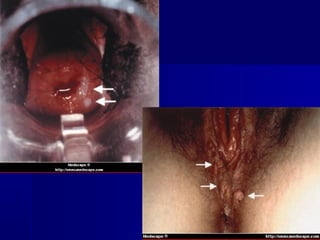

HPV

DST não objeto da abordagem sindrômica

Verrugas anogenitais-HPV

Fontes: http://dermatlas.med   e CRT-DST-Aids

Câncer cervical - HPV

http://www.inctr.org/publications/images/2003_v03_n03_w03.jpg

CÂNCER ANOGENITAL

   NIC 3 ASSOCIADO A HPV

DST não objetoda abordagem sindrômica Verrugas anogenitais-HPV Fontes: http://dermatlas.med e CRT-DST-Aids

DST não objetoda abordagem sindrômica Câncer cervical - HPV http://www.inctr.org/publications/images/2003_v03_n03_w03.jpg

CÂNCER ANOGENITAL  NIC 3 ASSOCIADO A HPV 16